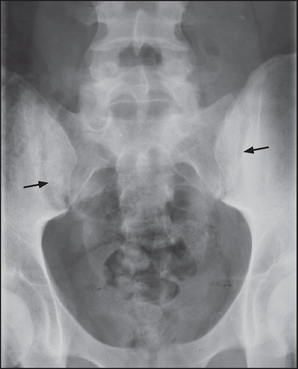

Figure 26.4 Ankylosing spondylitis Anteroposterior (a) and lateral (b) X-rays of the thoracic spine showing ankylosis of the sacroiliac joints, extensive syndesmophyte formation (short arrows) and squaring of the vertebral bodies (long arrows).

X-rays of the spine and sacroiliac joints (see Figure 26.4) may show ankylosis (fusion) of the sacroiliac joints and ‘squaring’ of the vertebral bodies as a result of loss of their anterior corners and periostitis of their waists. ‘Bridging syndesmophytes’a occur as a result of ossification of the fibres of the joint annulus. Severe disease causes the changes called bamboo spine visible on X-ray.